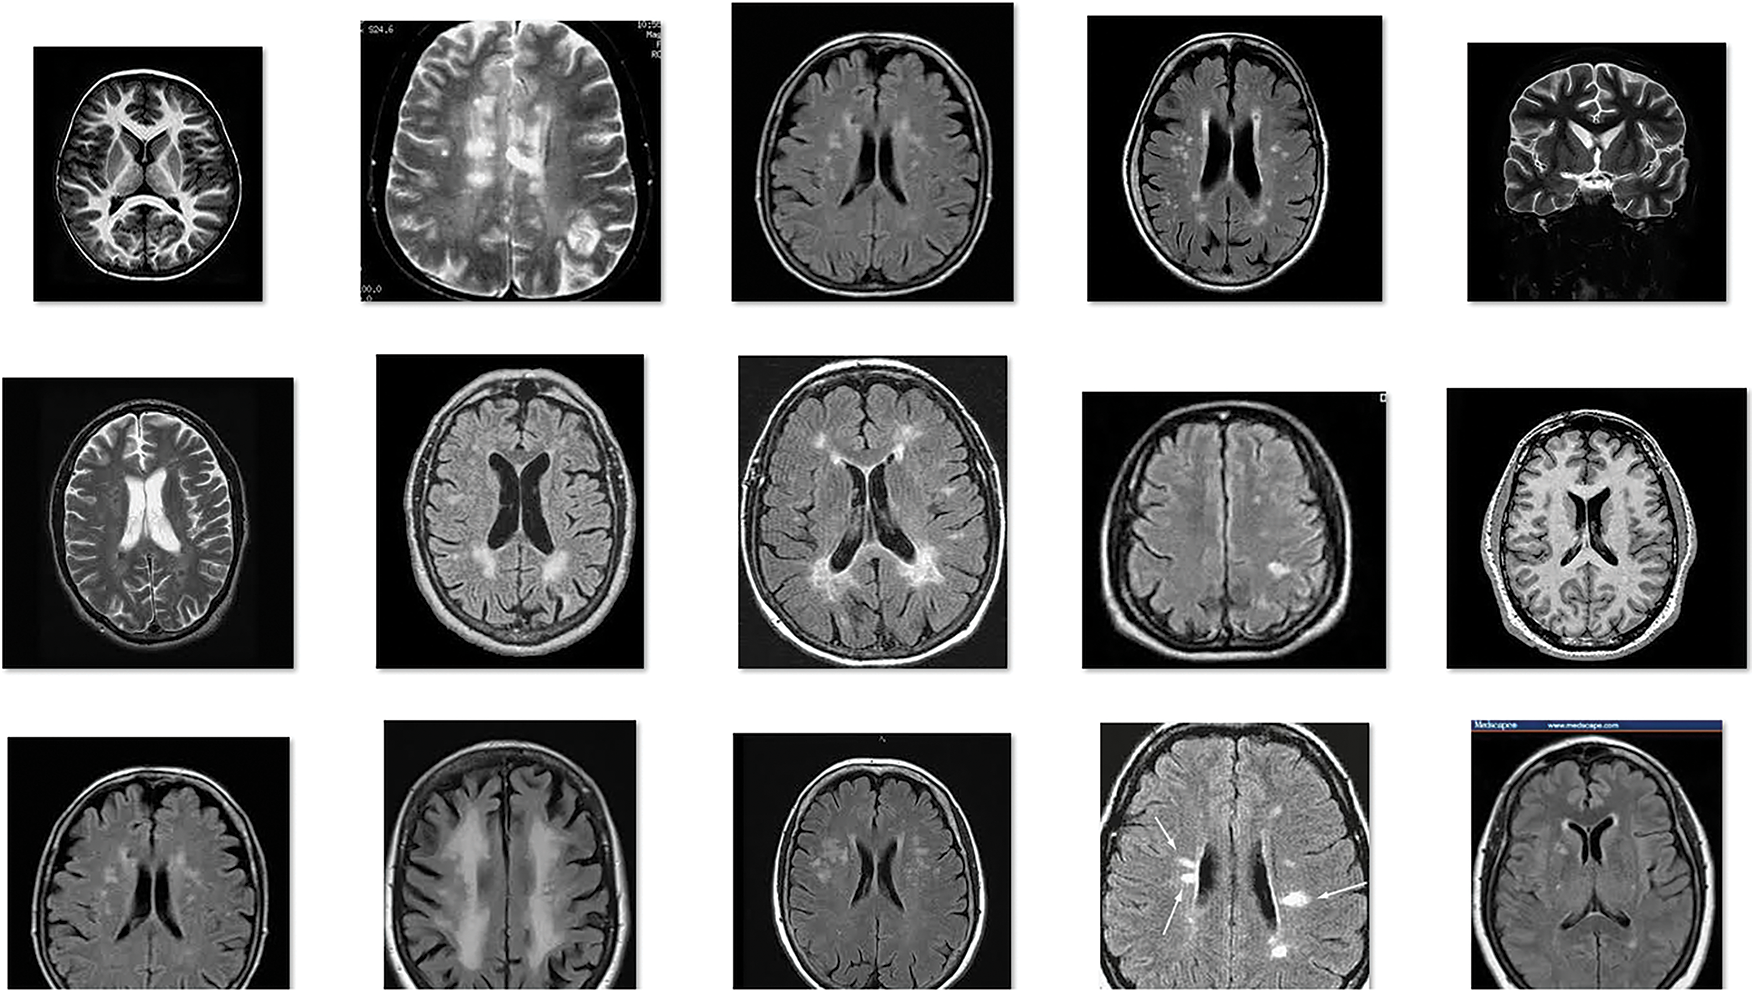

This section investigates the BT classification performance of the IoMTC-HDBT technique against benchmark BT dataset from Kaggle repository [23]. The dataset comprises 98 images under Normal class and 155 images under Abnormal class. The dataset includes images with the size of 192 * 192 to 630 * 630. Fig. 3 illustrates a few sample images.

Figure 3: Sample images